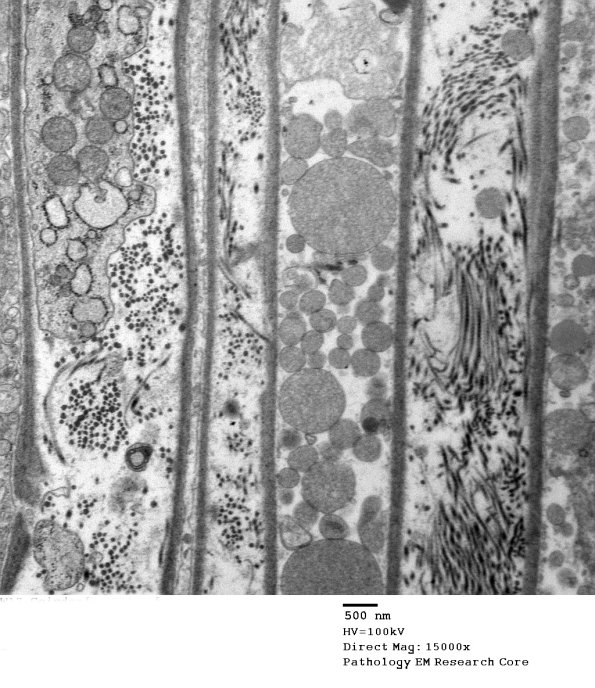

7C3A,B Are these processes of perineurial cells? - (electron micrographs)